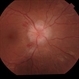

- optic nerve edema

Fundus camera

Topcon - Description